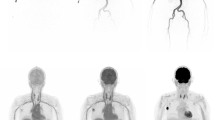

With the LAFOV PET-CT scanners, it is not necessary to define a FOV for the dynamic acquisition since the body trunk can be assessed with only one measurement. This means that an evaluation of radiotracer kinetics of all organs can be performed simultaneously. Especially in patients with extended metastatic disease, it is for the first time possible to measure simultaneously the tracer uptake in practically all tumor lesions and all organs (Fig. 4). This aspect is important particularly for therapy monitoring, drug development, and investigation of possible interactions between different organs, known as connectomes. Connectomes seem to have an impact also for non-oncologic applications. In a recent review paper, it was postulated that Parkinson disease (PD) is highly heterogenous and consists of several subtypes, which can be divided into a peripheral nervous system (PNS)-first and a central nervous system (CNS)-first subtype [31]. In this context, WB PET-CT studies may be helpful to identify the subtype of PD.

Dynamic [18F]-FDG PET-CT study in a patient with metastatic melanoma. Serial torso images from 45 s to 60 min p.i. demonstrate the high temporal resolution of the LAFOV scanner in the first seconds of dPET acquisition with the delineation of the large arterial vessels as well the gradual increase of the tracer uptake in the tumor lesions up to 60 min. PET angiography based on early dynamic PET-CT images may become an option for vascular evaluation, given the satisfying spatial and temporal resolution of the LAFOV systems

Improved temporal resolution

LAFOV scanners provide a higher time resolution than conventional systems, which means that it is easily possible after the list mode acquisition to reconstruct very short images defined by the users with a good image quality. Exemplary, at out institution we use a Biograph Vision Quadra (Siemens Healthineers) and reconstruct normally 33 frames with an increasing frame duration, starting from the time of tracer injection up to 60 min post-injection (p.i.) for [18F]- and [68Ga]-labeled radiopharmaceuticals (10 × 15 s, 5 × 30 s, 5 × 60 s, 5 × 120 s, 8 × 300 s).